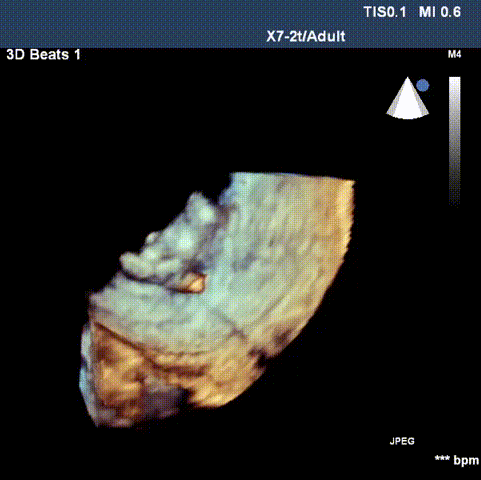

超声检查

患者二尖瓣机械瓣瓣周可见两处间隙,分别位于10点位、1-2点位,大小分别约为:10点位7×5mm,1-2点位10×4mm,彩色血流提示二尖瓣位瓣周返流(两束,大量),主动脉瓣位机械瓣上血流速度正常,瓣周未见明显返流。

心脏超声可见两处二尖瓣瓣周漏